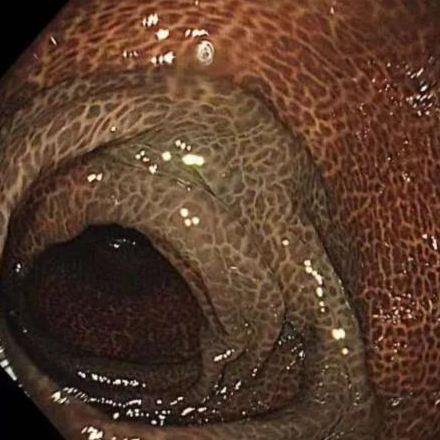

季女士整条大肠内壁

呈现出棕黑色蛇皮样

黑色素沉着明显

被诊断为"结肠黑变病"

正常的结肠黏膜就像口腔黏膜一样,是淡红色的,看起来光滑平坦,黏膜表面的小血管纹理清晰可见。

结肠黑变病的肠黏膜色泽呈现棕色、褐色,有豹纹或者蛇皮一样的条状纹,严重的甚至会变成黑色。

结肠黑变病是因为结肠壁的吞噬细胞吞噬了褐色素样物质,导致肠壁色素沉着。通俗点说,就是大肠吃多了色素,就变成了黑肠。此外,直肠前突、肠套叠、溃疡性结肠炎等其他疾病也可能导致黑变病。